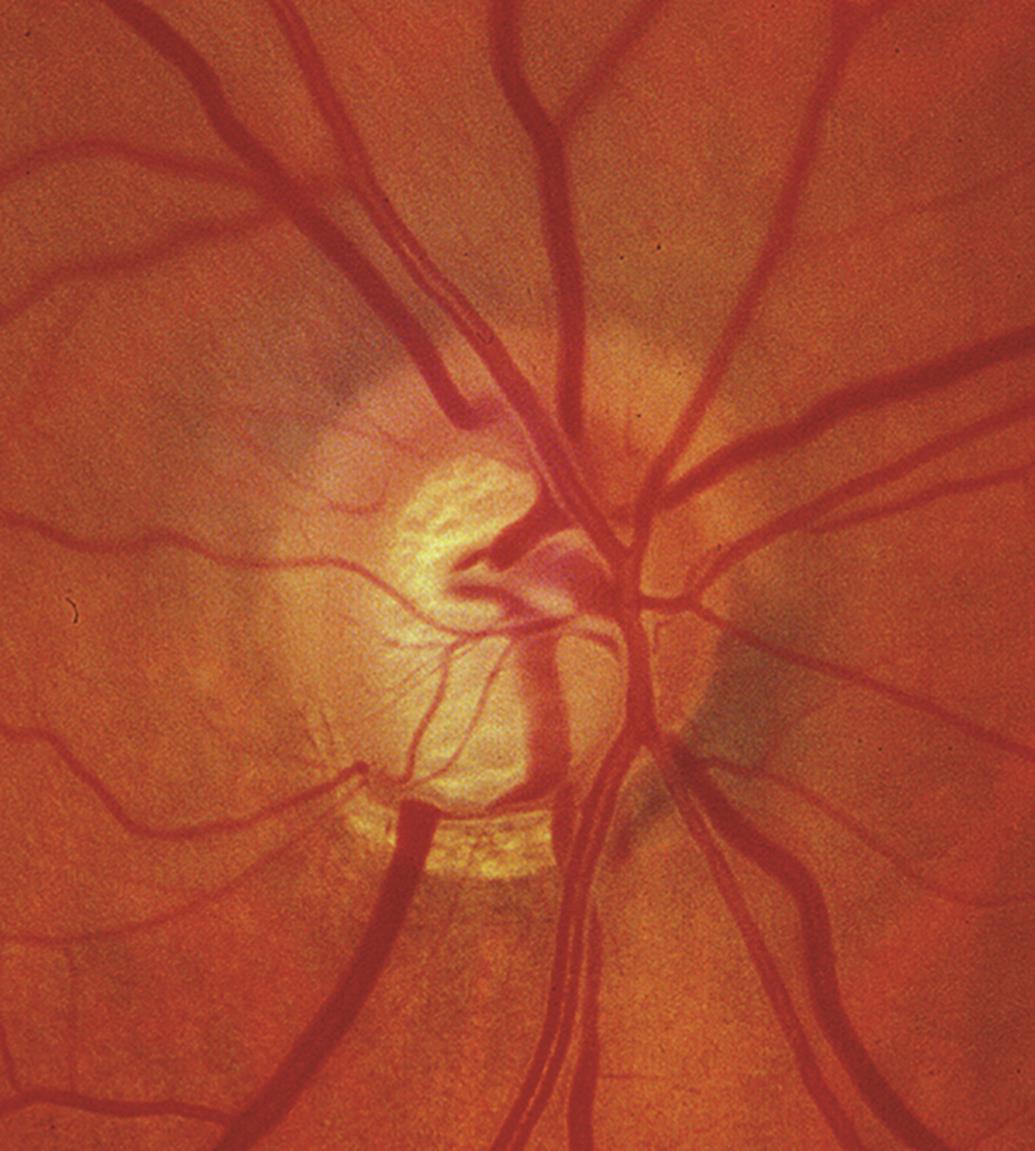

<후천성 시신경 유두오목 (Acquired Pit of the Optic Nerve, APON, Pseudopit)>

Pit 라는 것은 구멍 혹은 구덩이라고 하여, 크고 깊은 구덩이를 의미하는 용어입니다.

이는 시신경부위를 깊은 구덩이를 판것처럼 깊게 패인 부분이 발생하는 경우를 말합니다.

APON은 단순한 망막섬유층의 패임(notching)정도보다 더 깊게 패이는 것으로,

사상판에 도달할 정도와, 시신경유두의 가장자리에 닿을 정도로 국소적인 망막신경섬유층의 상실이 있음을 의미합니다.

즉, 사상판 위쪽에 존재해야하는 망막신경섬유층이 완전히 상실되면서,

사상판이 완전히 노출되는 것으로, 하얀게 사상판 조직을 직접 관찰할수 있습니다.

1/3에서는 시신경유두의 상극단의 귀쪽에서,

2/3에서는 시신경유두의 하극단의 귀쪽에서, 발견되는데,

보통은 APON 이 발생한 부위에서는

해당부위에 이전에 시신경유두의 선상출혈이 발생하였다가 출혈이 없어지고난뒤에 발견하는 경우가 종종 있습니다.

이는 사상판의 특정 부분이 안압 상승에 대한 저항이 적어서 발생하게되는것으로,

해당부위가 압력에 의해서 눌리면서 구덩이가 발생하는 것입니다.

APON을 가진 녹내장환자의 96%에서 시야 중심 5도내의 짙은 시야 결손이 동반되며,

APON을 가진 녹내장환자의 경우 APON이 없는 환자보다 유의하게 손상이 진행되며, 시시녕 유두출혈도 더 많이 동반됩니다.